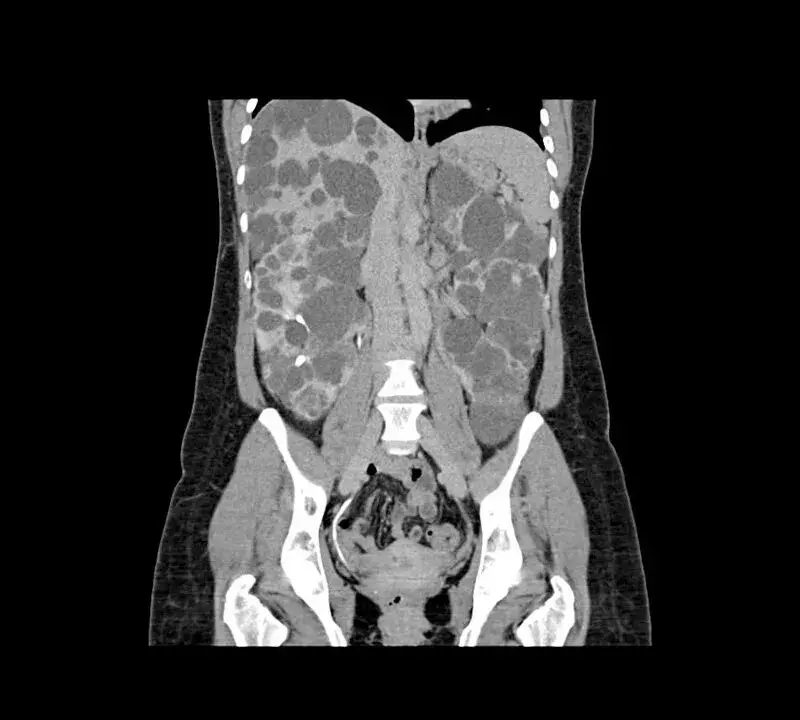

doenca renal policistica